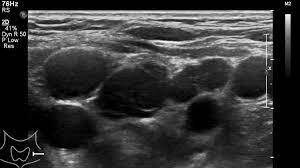

Cureus Evaluation Of B Mode And Color Doppler Ultrasound In The Diagnosis Of Malignant Cervical Lymphadenopathy

Cureus Evaluation Of B Mode And Color Doppler Ultrasound In The Diagnosis Of Malignant Cervical Lymphadenopathy from assets.cureus.com

But, can this imaging test actually detect cancer? Neck lumps are a common presentation in the general population, presenting in both children and adults, and have a wide range of potential differential diagnoses. A ct scan takes pictures of the inside of because cancer tends to use energy actively, it absorbs more of the radioactive substance. These sound waves are not detectable by human hearing. Lung cancer tend to be found in the lungs. Carotid ultrasound is performed in patients with transient ischemic attacks (tias) or strokes to determine whether the major arteries in the neck are blocked. Ultrasound is sound waves with frequencies higher than the upper audible limit of human hearing. Sometimes the cancer cells can spread into the nearby lymph nodes.

An ultrasound of the neck uses high frequency sound waves to create a live image from inside of a patient's body. These sound waves are not detectable by human hearing. Sometimes the cancer cells can spread into the nearby lymph nodes. It can detect abnormal tissues, growths, and cysts and give a suspicion of. An ultrasound uses sound waves to create a picture of internal organs. What an ultrasound can detect? Computed tomography (ct or cat) scan. Similarly, being able to identify precancerous tissue abnormalities accurately. Ultrasound may be used to guide a needle into pockets of fluid accumulated in the body that need to be drained (for example, an abscess, pleural effusions, or ascites). An mri produces sharp, detailed images that can help detect cancerous cells in the head and neck. Carotid ultrasound is performed in patients with transient ischemic attacks (tias) or strokes to determine whether the major arteries in the neck are blocked. Diagnostic imaging for head and neck cancer. But the results are dependent on the experience of the sonographer(radiologist).